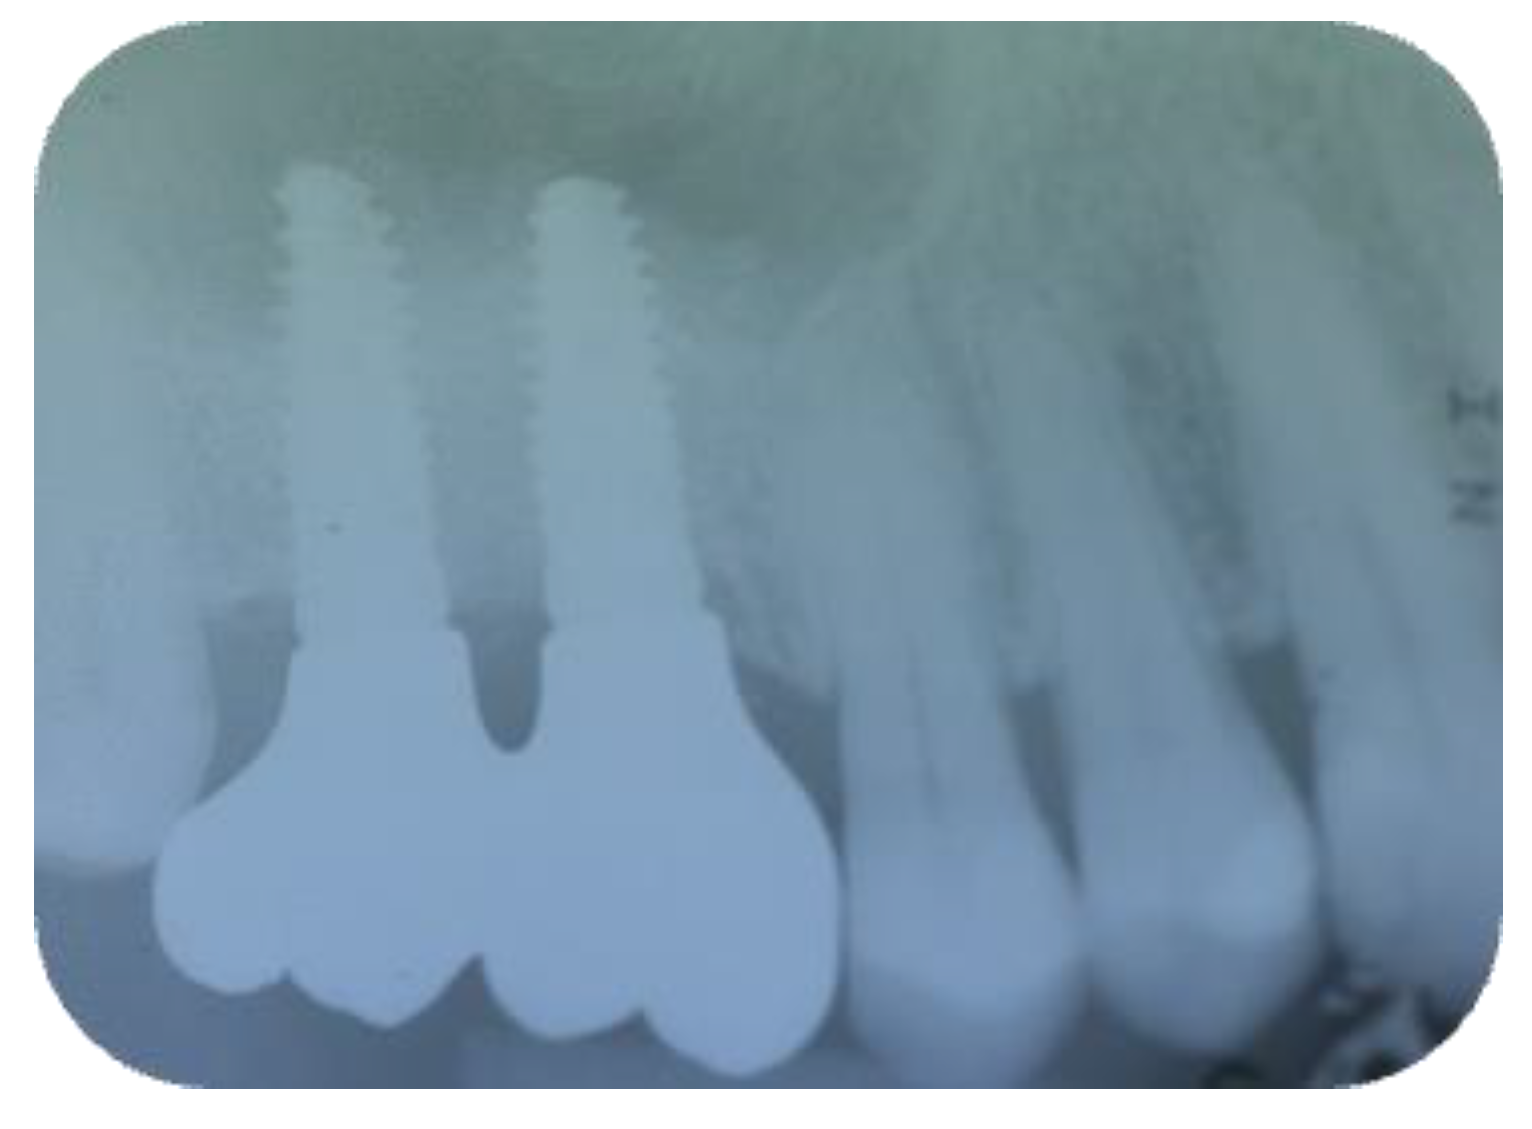

2.1. Surgical Procedures

2.2. Follow-Up

3. Results